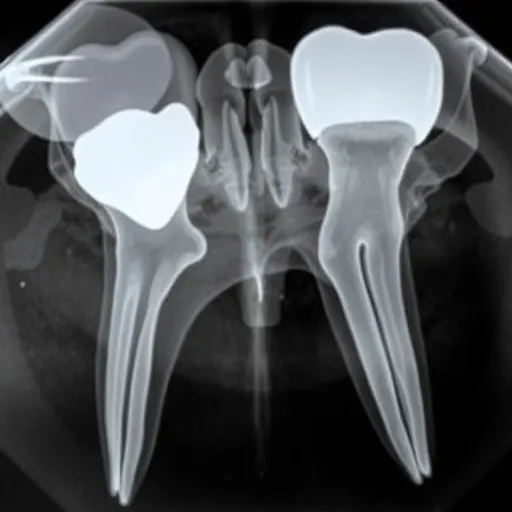

매복 사랑니충치가 의심될 경우, X-ray 또는 3차원 CT 촬영을 통해 사랑니와 제2대구치 사이의 충치 진행 상황을 정확히 파악해야 합니다. 충치가 제2대구치에까지 전이되었지만 아직 깊지 않다면, 사랑니를 발치한 후 제2대구치의 손상된 부분만 보존적으로 치료할 수 있습니다. 하지만 충치가 제2대구치의 치수(신경)까지 깊숙이 침범했다면, 제2대구치 역시 신경 치료를 하거나 최악의 경우 발치를 고려해야 하는 상황에 놓일 수 있습니다.